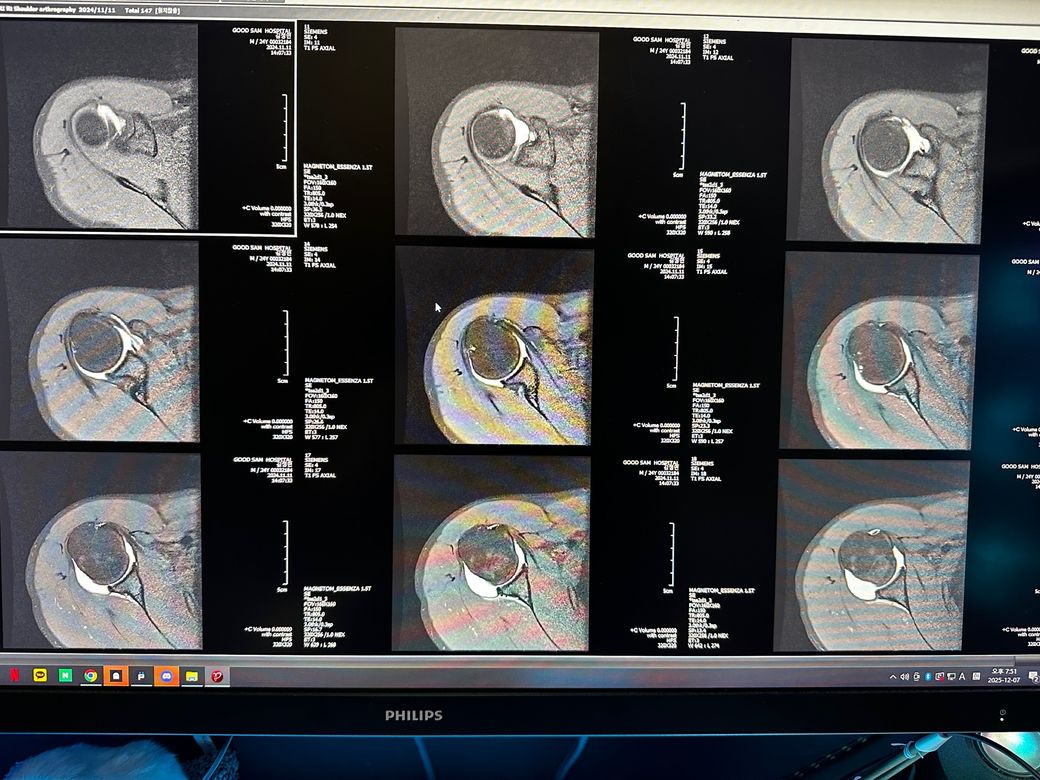

오른쪽어깨 관절mri좀 봐주세요 사진첨부입니다

오룬쪽어깨관절 엠알아이 결과좀 봐주세요

오른쪽어깨관절부분입니다

관절입니다

• 10번 째 사진

• 11번 째 사진

• 12번 째 사진

조영제가 들어간 것으로 보이며, "회전근개(특히 극상근) 파열이나 큰 손상은 뚜렷하게 보이지 않는 편"입니다.

관절와순(Labrum) 주변에 조영제가 퍼져 보이지만, "명확한 파열 소견은 사진만으로 단정 어렵고 경미한 손상.염증 가능성"은 있습니다.

관절 안쪽에 "약한 염증/활액 증가"는 있어 보이며, 충돌증후군 초기 형태 가능성이 있습니다.